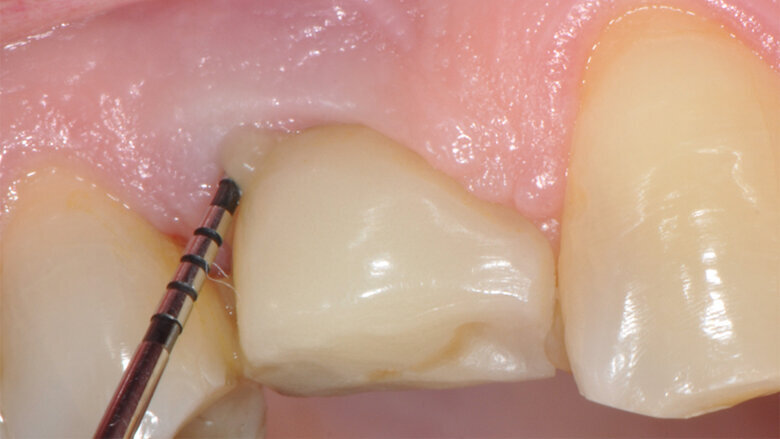

Fig.10: Case 1. Healing at 6 months after MAINST therapy. PPD has decreased to 2mm. BOP and suppuration are absent.